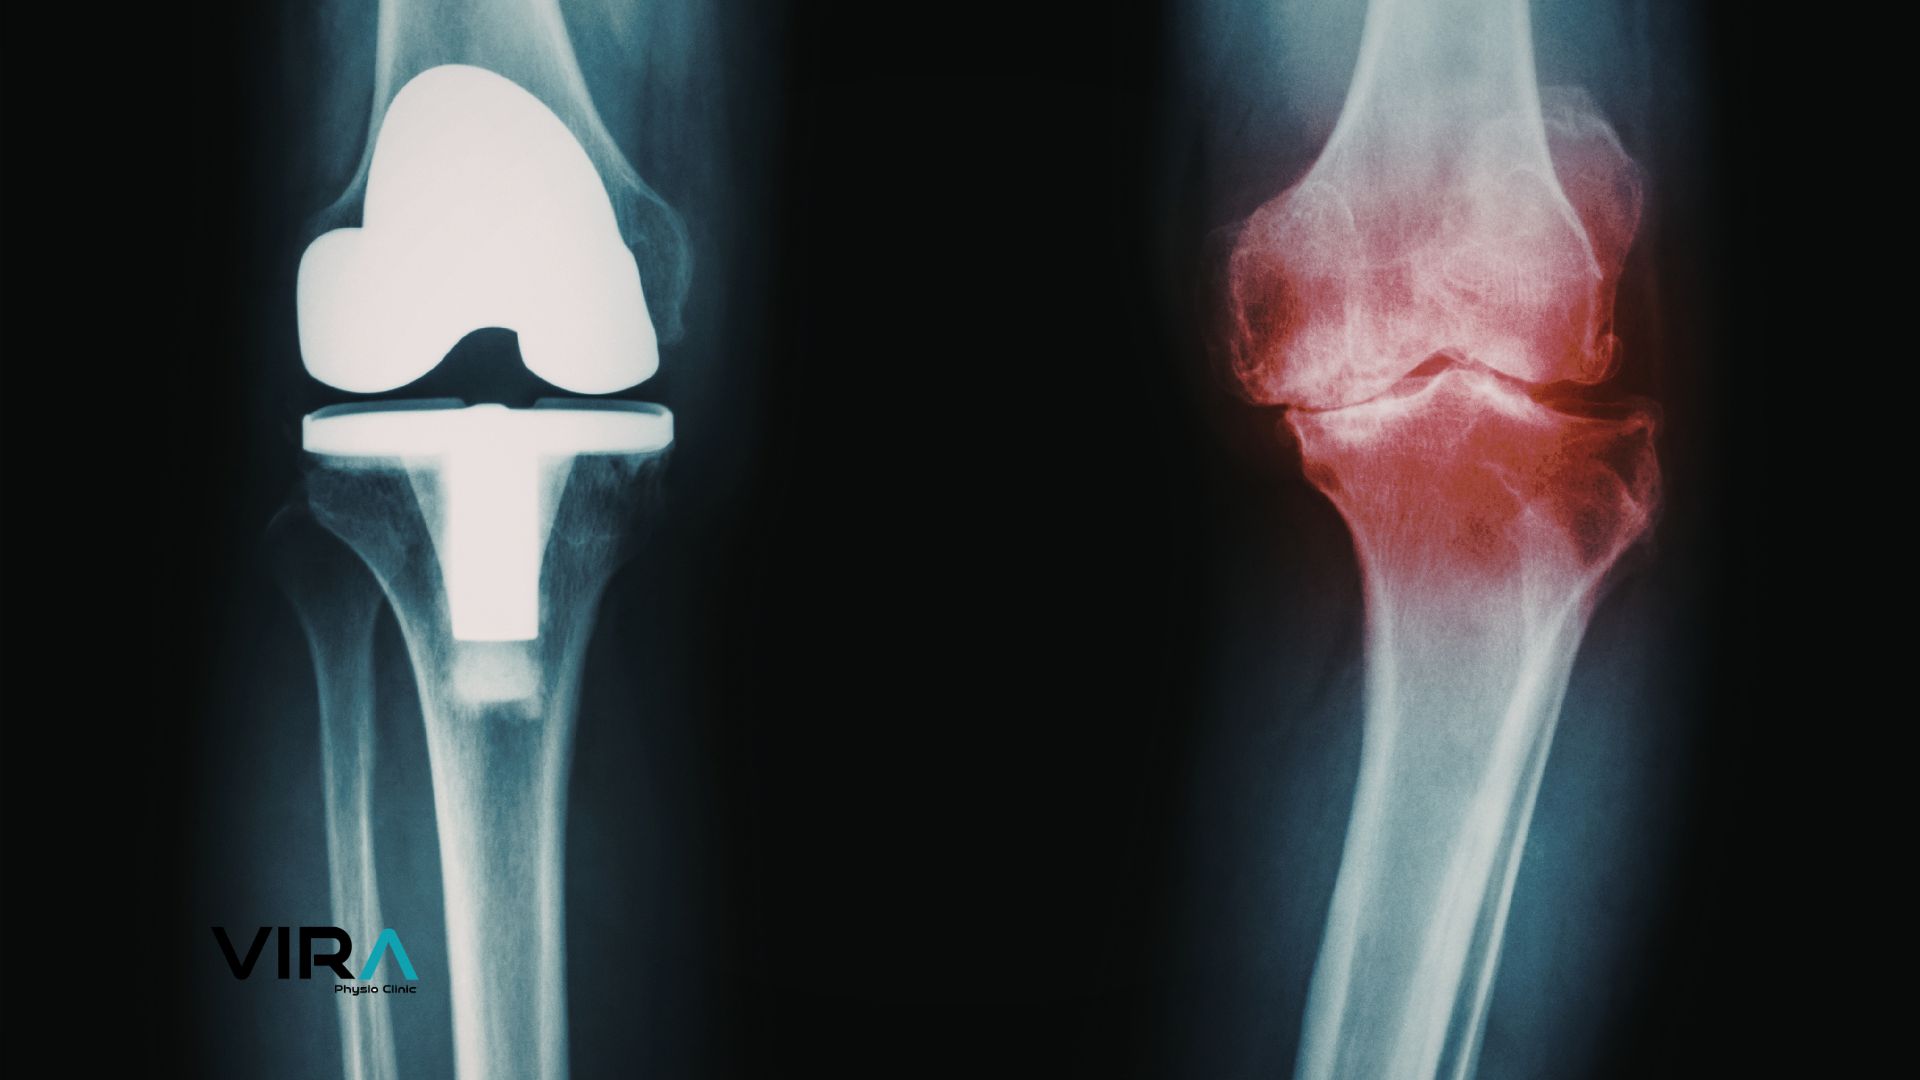

تعویض مفصل زانو یا آرتروپلاستی کامل مفصل زانو که با نام علمی Total Knee Arthroplasty (TKA) شناخته میشود، یکی از پیشرفتهترین جراحیهای ارتوپدی برای درمان تخریب شدید مفصل زانو است. در این روش درمانی که امروزه بهعنوان استاندارد طلایی درمان آرتروز پیشرفته شناخته میشود، سطوح مفصلی استخوان ران (فمور) و درشتنی (تیبیا) که دچار تخریب غضروفی شدهاند، با اجزای مصنوعی دقیق و مهندسیشده جایگزین میگردند تا درد بیمار کاهش یافته و عملکرد حرکتی وی بهبود پیدا کند. افرادی که در تهرانپارس و شرق تهران با درد مزمن زانو، محدودیت حرکتی و تغییر شکل اندام تحتانی مواجه هستند، معمولاً پس از عدم پاسخ به درمانهای دارویی، تزریقی و فیزیوتراپی، کاندید انجام تعویض مفصل زانو در تهرانپارس میشوند.

تعویض کامل مفصل زانو شایعترین نوع جراحی در مراکز تخصصی تعویض مفصل زانو در شرق تهران است. در این روش، تمام سطوح مفصلی آسیبدیده استخوان ران و درشتنی با اجزای فلزی و پلیاتیلنی جایگزین میشوند و در صورت نیاز سطح کشکک نیز تعویض میگردد. این روش برای بیماران مبتلا به آرتروز پیشرفته، تغییر شکل شدید زانو یا بیماریهایی مانند Rheumatoid arthritis مناسب است. تعویض کامل مفصل زانو باعث کاهش چشمگیر درد و بهبود پایدار عملکرد حرکتی میشود.